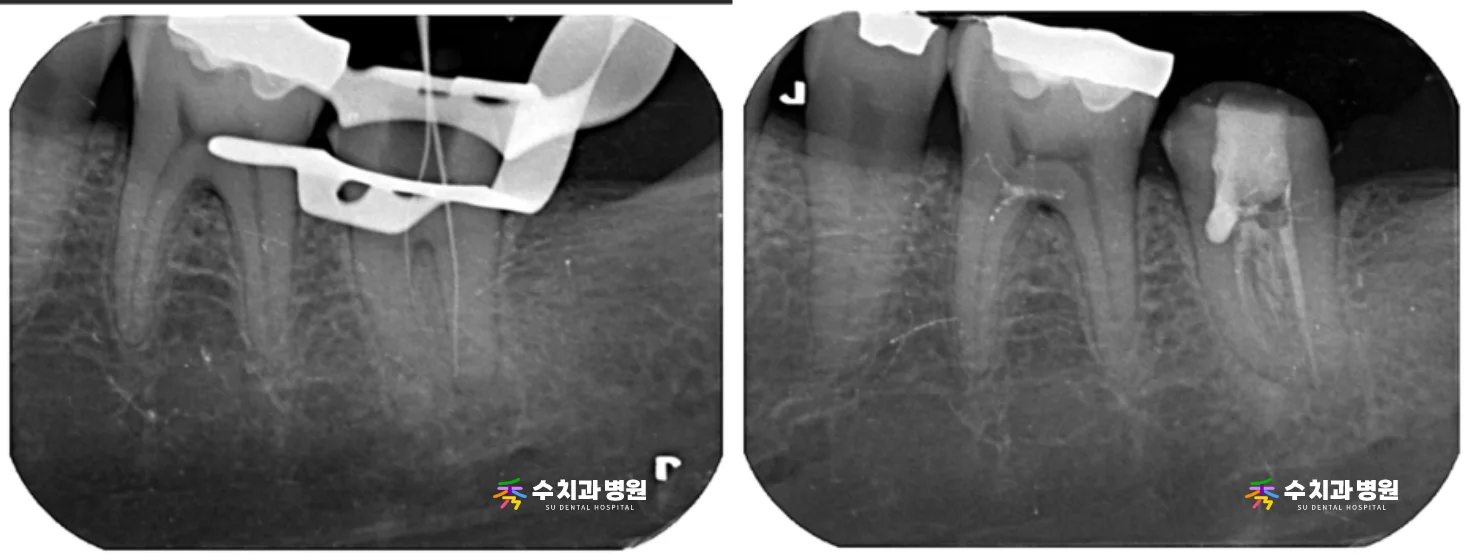

[신경치료 사진] (촬영일: 2025년 6월)

[치료 전후 비교 사진] (촬영일: 전 2025년 5월 / 후 2025년 6월)